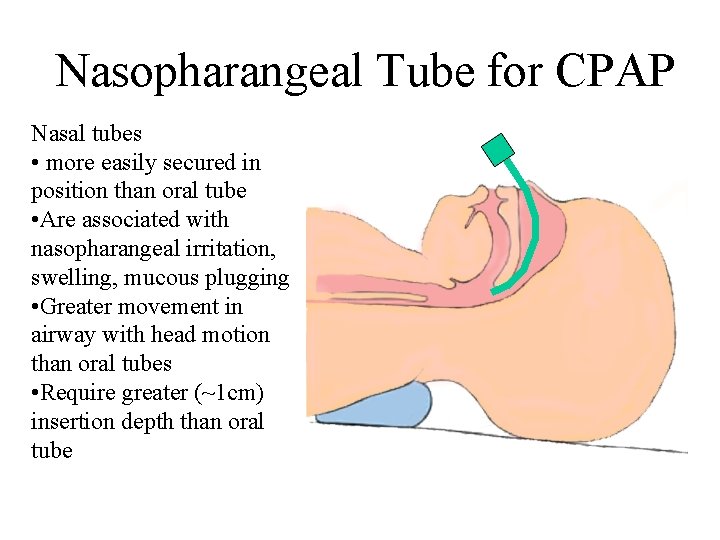

Nasopharangeal Tube for CPAP Nasal tubes • more easily secured in position than oral tube • Are associated with nasopharangeal irritation, swelling, mucous plugging • Greater movement in airway with head motion than oral tubes • Require greater (~1 cm) insertion depth than oral tube